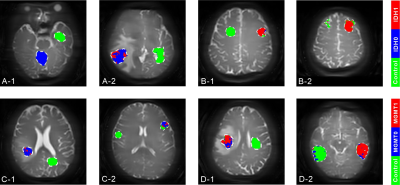

本研究提出了一种基于化学交换饱和转移(CEST)的深度学习方法,旨在体素水平上精准预测胶质瘤患者的IDH突变和MGMT甲基化状态。通过对86名患者进行的3T MRI扫描的CEST实验,我们开发了一个高效的CEST深度学习模型,用于预测IDH和MGMT状态。研究结果显示,该方法相较于现有CEST预测技术,展现出更高的准确性,并通过混淆矩阵和ROC曲线进行了性能评估该方法不仅有助于胶质瘤的精确诊断,还降低了对大量训练数据的需求,并提升了预测速度,对治疗决策和患者生存率预测具有重要的临床价值。

f8dc4fd66c549330ab771f55600bf1aa.png

8名测试患者数据的预测图。肿瘤和对照区域由经验丰富的神经放射科医师勾画。

A-1和A-2代表携带IDH野生型的患者,而B-1和B-2代表携带IDH突变的患者。

C-1和C-2是没有MGMT甲基化的病人,D-1和D-2是有MGMT甲基化的病人。